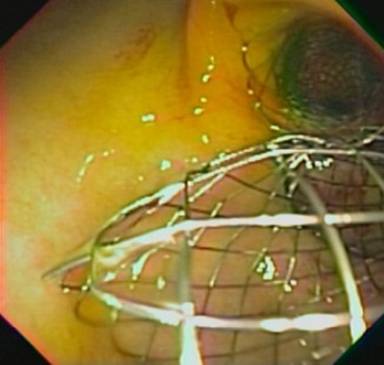

Upper endoscopy had previously shown duodenal stenosis due to circumferential ulcerated and infiltrative lesions in all cases. Facing a high probability of an unsuccessful ERCP, we discussed the possibility of endosonography-guided biliary drainage and duodenal stenting with the surgical and oncological teams. We performed the procedure following the same sequence in all cases. For the whole procedure, the patient was under general anesthesia and fluoroscopic guidance was used. A therapeutic duodenoscope (TJF-160, Olympus, Tokyo, Japan) was introduced and advanced until the duodenal bulb. A 0.035 guidewire (Jagwire®, Boston Scientific, Natick, MA, USA) was advanced through the duodenal stenosis until the proximal jejunum (Figure 1). The stenosis was dilated with a dilation balloon (CRETM Balloon Dilator, Boston Scientific, Natick, MA, USA) until 15 mm. The duodenoscope was advanced but the major ampulla could not be identified. The guidewire was left in place and the duodenoscope was removed. A linear array echoendoscope (GF UCT-140, Olympus, Tokyo, Japan; Alfa 5 processor, Aloka, Tokyo, Japan) was introduced. Endosonography examination was performed to look for the dilated common bile duct, the largest left intrahepatic duct and the presence of collateral veins. In all cases, the largest left intrahepatic ducts were smaller than 6 mm and we did not attempt the antegrade transhepatic access. The common bile duct was punctured with a 19-gauge needle (EUSN-19T, Cook Medical, Bloomington, IN, USA) (Figure 2). Bile was aspirated and contrast was injected to confirm an adequate position of the needle (Figure 3). After confirmation with fluoroscopy, a 0.035 guidewire (Jagwire®, Boston Scientific, Natick, MA, USA) was advanced through the needle into the common bile duct and the needle was retrieved. A 6-Fr cystotome (Endo Flex, Voerde, Germany) was then inserted over the guidewire to create a bilioenteric communication (Figure 4). In four patients, a partially covered biliary self-expandable metallic stent (WallFlex® 60/100 mm, Boston Scientific, Natick, MA, USA) was inserted into the common bile duct and successfully deployed, creating a choledochoduodenal fistula (Figure 5). In one patient (Patient#2), we deployed an uncovered biliary metallic stent (WallFlex® 60/100 mm, Boston Scientific, Natick, MA, USA). The echoendoscope was removed and the duodenoscope was introduced over the duodenal guidewire. A non-covered duodenal self-expandable metallic stent (WallFlex® 120/220 mm, Boston Scientific, Natick, MA, USA) was inserted over the guidewire and deployed in all patients (Figures 6 and 7).

Figure 5. Deployed biliary stent. |

Figure 6. Deployed biliary and duodenal stents. |